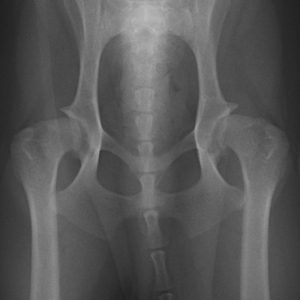

犬の股関節形成不全 股関節異形成とも言われ、主に大型犬種に多く見られる発育期の疾患です。 チワワ、ダックス、ヨークシャー・テリア、トイ・プードル、ボストンテリア、ペキニーズなど 人気の小型種・短頭種に、先天性水頭症としての発生が多い傾向にあります。. 股関節形成不全とは? 股関節形成不全とは犬が発育の途中に股関節の形成に異常をきたしてしまう事で発症します。 この股関節の形態的な異常は、犬の体に様々な症状を発症させます。 股関節形成不全の発症は、一般的に両側の股関節で発症することが多くあります。 しかし場合によっては 片方の股関節だけが、股関節形成不全に陥る 可能性もあります。 この. 股関節形成不全とは、股関節の形態的な異常のこと。痛みを伴なうことがあり、犬の生活の質を大幅に低下させる恐れがあります。 この記事の監修者 みずの動物クリニック 水野範仁(みずの のりひと) 酪農学園大学獣医学科 修士課程修了 途中までちがう道を志すも若き青年の心を打ち壊す.

仕事柄、たくさんの犬達を見る機会が多いのですが股関節形成不全の子を 見るたびグルコサミン350をお勧めしています。 今、嬉しそうに遊びまわる愛犬を見ているとあの時がウソのようです。 ***ライフパークお客様担当より***. いぬのこかんせつけいせいふぜん(こかんせつけいせいいじょう) 犬の股関節形成不全(股関節形成異常) 股関節形成不全(股関節形成異常)は、股関節が正常に形成されていないことや変形することにより、歩き方などに異変を起こす病気です。 遺伝や環境的な要因が考えられ、おもにジャーマン・シェパード、ラブラドール・レトリーバー、ゴールデン. Jul 11, 16股関節形成不全とは、太ももの骨と骨盤とを結合する股関節がうまく作られず形が異常になってしまう、発育や成長の異常です。 この病気は小型犬より大型犬に多く発症します。.